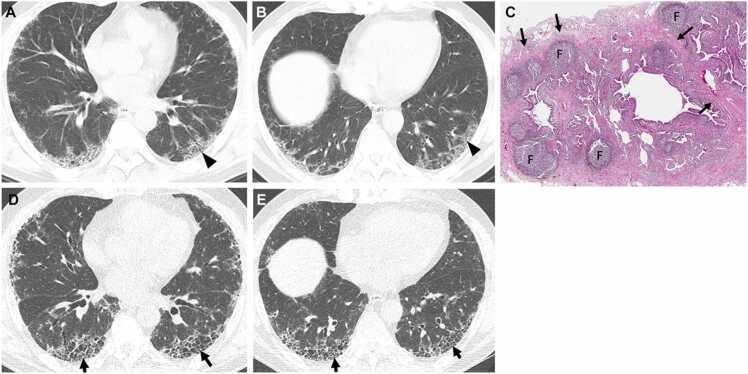

Connective tissue diseases (CTDs) demonstrating features of interstitial lung disease (ILD) include systemic lupus erythematosus (SLE), rheumatoid arthritis (RA), systemic sclerosis (SSc), dermatomyositis (DM) and polymyositis (PM), ankylosing spondylitis (AS), Sjogren syndrome (SS), and mixed connective tissue disease (MCTD). On histopathology of lung biopsy in CTD-related ILDs (CTD-ILDs), multi-compartment involvement is an important clue, and when present, should bring CTD to the top of the list of etiologic differential diagnoses. Diverse histologic patterns including nonspecific interstitial pneumonia (NSIP), usual interstitial pneumonia (UIP), organizing pneumonia, apical fibrosis, diffuse alveolar damage, and lymphoid interstitial pneumonia can be seen on histology in patients with CTD-ILDs. Although proportions of ILDs vary, the NSIP pattern accounts for a large proportion, especially in SSc, DM and/or PM and MCTD, followed by the UIP pattern. In RA patients, interstitial lung abnormality (ILA) is reported to occur in approximately 20-60% of individuals of which 35-45% will have progression of the CT abnormality. Subpleural distribution and greater baseline ILA involvement are risk factors associated with disease progression. Asymptomatic CTD-ILDs or ILA patients with normal lung function and without evidence of disease progression can be followed without treatment. Immunosuppressive or antifibrotic agents for symptomatic and/or fibrosing CTD-ILDs can be used in patients who require treatment.

表现为间质性肺疾病(ILD)特征的结缔组织病(CTD)包括系统性红斑狼疮(SLE)、类风湿关节炎(RA)、系统性硬化症(SSc)、皮肌炎(DM)和多发性肌炎(PM)、强直性脊柱炎(AS)、干燥综合征(SS)以及混合性结缔组织病(MCTD)。在CTD相关ILD(CTD-ILD)的肺活检组织病理学检查中,多部位受累是一个重要线索,若出现这种情况,应将CTD列为病因鉴别诊断的首要考虑。CTD-ILD患者的组织学检查可见多种组织学模式,包括非特异性间质性肺炎(NSIP)、寻常型间质性肺炎(UIP)、机化性肺炎、肺尖纤维化、弥漫性肺泡损伤和淋巴细胞间质性肺炎。尽管ILD的比例各不相同,但NSIP模式占很大比例,尤其是在SSc、DM和/或PM以及MCTD中,其次是UIP模式。据报道,RA患者中约20%-60%会出现间质性肺异常(ILA),其中35%-45%的患者CT异常会进展。胸膜下分布以及基线时ILA受累程度较高是与疾病进展相关的危险因素。无症状的CTD-ILD或ILA且肺功能正常且无疾病进展证据的患者可以不进行治疗而进行随访。有症状的和/或纤维化的CTD-ILD患者若需要治疗,可使用免疫抑制剂或抗纤维化药物。